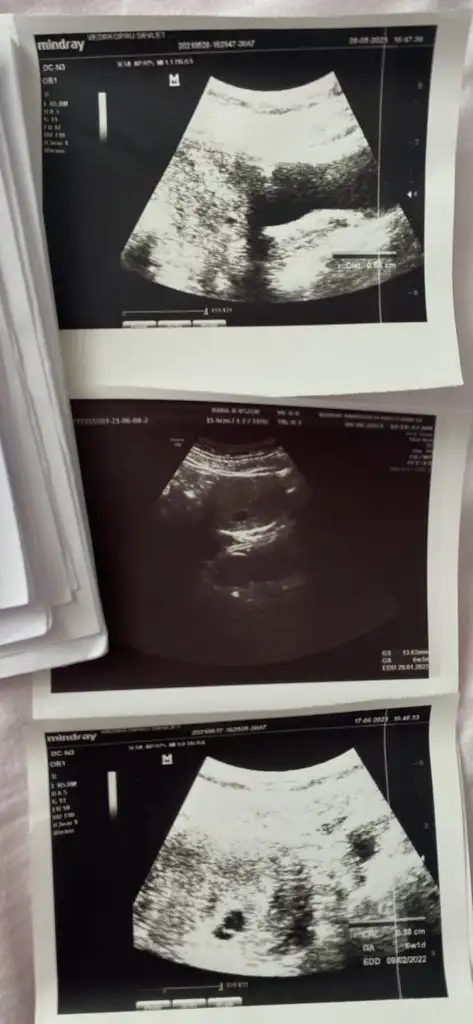

Merhaba ben 15 Nisanda kürtaj oldum.Adet olmadan kürtajdan 40 gün sonra hamile olduğumu öğrendim 25 Mayısta kese karından görünmedi alttan bakınca doktor yeni oluşan bi kese olduğunu düşündü 28 mayısta karından keseyi gördü.Keseye göre 5 hafta dedi.(5 hafta olma imkanı yoktu ama adet tarihine göre hesaplamadan dolayı 2 hafta fazla gibi hesaplandığından galiba ) 2 hafta sonra gel kalbine bakalım dedi.İlk hamileliğimde 6+2 de bebeğin kalbi durmuştu bende dayanamadım 11 gün sonra (8 Haziranda) 6+4 olması gereken zamanda özele gittim. Doktor henüz kesenin küçük olduğunu 20 mm olduğunda kalp atışının duyulduğunu söyledi.Keseye göre 6+3 tü bir güne takılmadım cihazdan da farkedebilir.Bebek çok küçük bir nokta şeklindeydi tutunmuş dedi. 2-3 hafta sonra gel dedi kalp için. 1 hafta geçtikten sonra ben devlete gittim. Kendi göründüğüm doktorun işi çıkmış gitmiş. Başka bir doktora göründüm ama o doktora hiç güvenmiyorum baktı daha kalp atışı yok 2 hafta sonra gel dedi kaç haftalık göründüğünü sordum 5+6 dedi (normalde 7. Haftada olması lazım) durumu anlattım bir hafta öncesinde 6+3 dendiğini doktor benim cihazımda ben bu şekilde ölçtüm 2 hafta sonra gel demekten başka bir şey söylemedi. Tabi haftasını o şekilde söyleyince ben kafamda bitirdim yine kalbi durdu diye düşündüm.O günden sonra kahverengi lekelenme başladı akıntının içinde kan görünce ben bebeği düşüreceğimi düşündüm korktum. Devletteki diğer doktor gelmişti ona gittim durumu anlattım baktı kese düzgün görünüyor dedi. Özelde çok küçük bi noktada olan bebek daha belirgin görünüyordu bu sefer Keseye göre değil de bebeğe göre ölçtü 6+1 çıktı 2 gün önceki ile de uyumluydu ama önceki haftalarla uyumlu değil. Kalp atışı yine yoktu.Kendimce düşünüyorum diğerlerinde Keseye göre ölçülmüştü şimdi bebeğe göre ölçüldüğü için mi acaba diyorum ama kese 8 haziranda da 17 haziranda da 13 mm idi. Kese gelişmeden bebek gelişir mi anlamadım. Doktor progestan verdi 1 hafta sonra gel dedi dinlenmemi bol su içmemi ilişkiye girmememi söyledi. Progestanı kullanıyorum ama acaba ölü bebeği mi karnımda tutuyorum ilaç kullanarak diye düşünüyorum.Güvenmediğim doktor hariç ultrason görüntülerini vermişti aşağıya ekledim birisi hariç diğerleri devlet. Bu konuda bilgisi olan benzer durum yaşayan yardımcı olur musunuzBen zaten kötüyü kabullendim gerçek neyse onu öğrenmek istiyorum